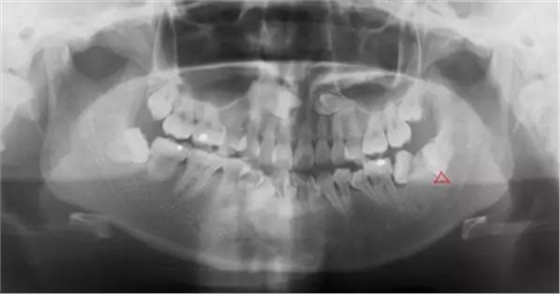

4.對頜牙缺失,智齒伸長

總而言之,需要拔除的智齒一般有以下幾種:

1.水平阻生影響前牙